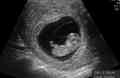

截止2020年底,西宁开展辅助生殖技术的医院共有2家,目前有青海省人民医院和青海红十字医院,支持夫精人工授精技术、第一代试管婴儿(常规体外受精-胚胎移植技术)、第二代试管婴儿(卵胞浆内单精子显微注射技术),暂未获得第三代试管婴儿(植入前胚胎遗传学诊断技术)的资质,如有相关生育需求,可根据自身实际情况就医。

辅助生殖技术的出现帮助越来越多的不孕不育家庭实现了生育梦,在青海省的试管医院中,目前西宁试管医院不多,唯一能开展人工授精和试管技术的是青海省人民医院和青海红十字医院,如果不孕不育家庭如果想在西宁做试管婴儿,建议综合考虑多个方面后再决定要不要在西宁做试管,如果仍觉得难以抉择,那么可以参考西宁本地助孕机构排名进行筛选。